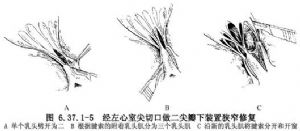

以上四型二尖瓣狭窄在婴幼儿也可经左心室切口,先劈开乳头肌,后劈开腱索或腱索开窗,最后将二尖瓣交界切开(图6.37.1-5)。